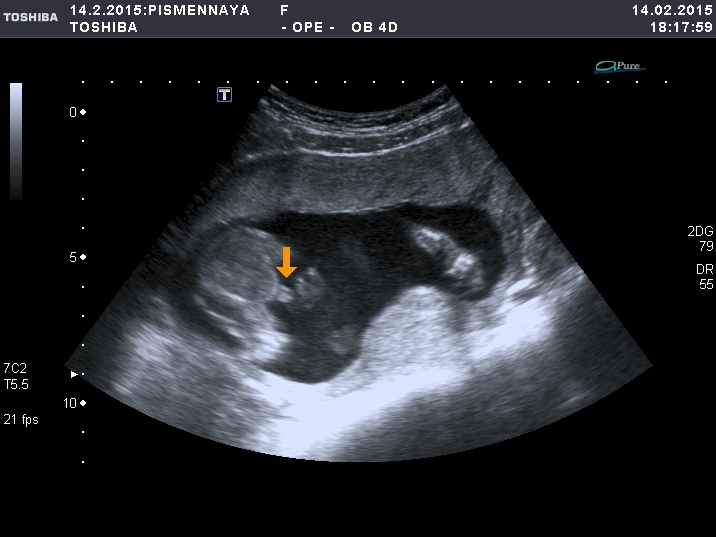

Девчули, кто делал узи на 16-17 неделях и узнал пол - гляньте, если не сложно поделитесь своими фотками. Я просто до сих пор не могу поверить, что наш Марк превратился в девочку!!! Может ошибка, кто помнит фото "бубенчиков"? Девочкины мамы - что скажите??? На фото две согнутые ноги и между ними стрелка указывает на половые органы, подписано "девочка".

явный пирожочек))))у меня такие же фотки были с дочками))))искать надо )))а вот сейчас в 15 недель сына пообещали,для меня разница очевидна ...они отличаются .Полосочек на моем снимке не видно,а вот яички висят))))